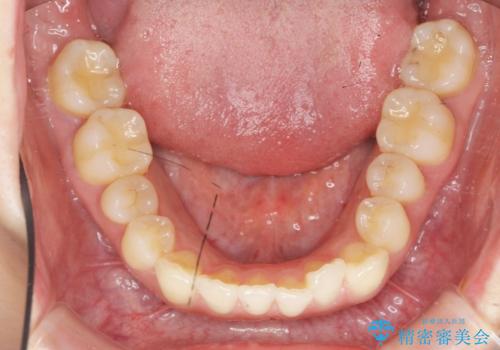

- 目立つ前歯のねじれを改善したい、と矯正治療を希望され来院されました。

マウスピース矯正インビザラインを用いて綿密に治療計画を練り、美しい歯並びを手に入れるべく治療計画を立案します。

左側の奥歯は後方移動を行うことで、理想的な噛み合わせに整えるとともに、前歯の突出感も同時に改善することができました。